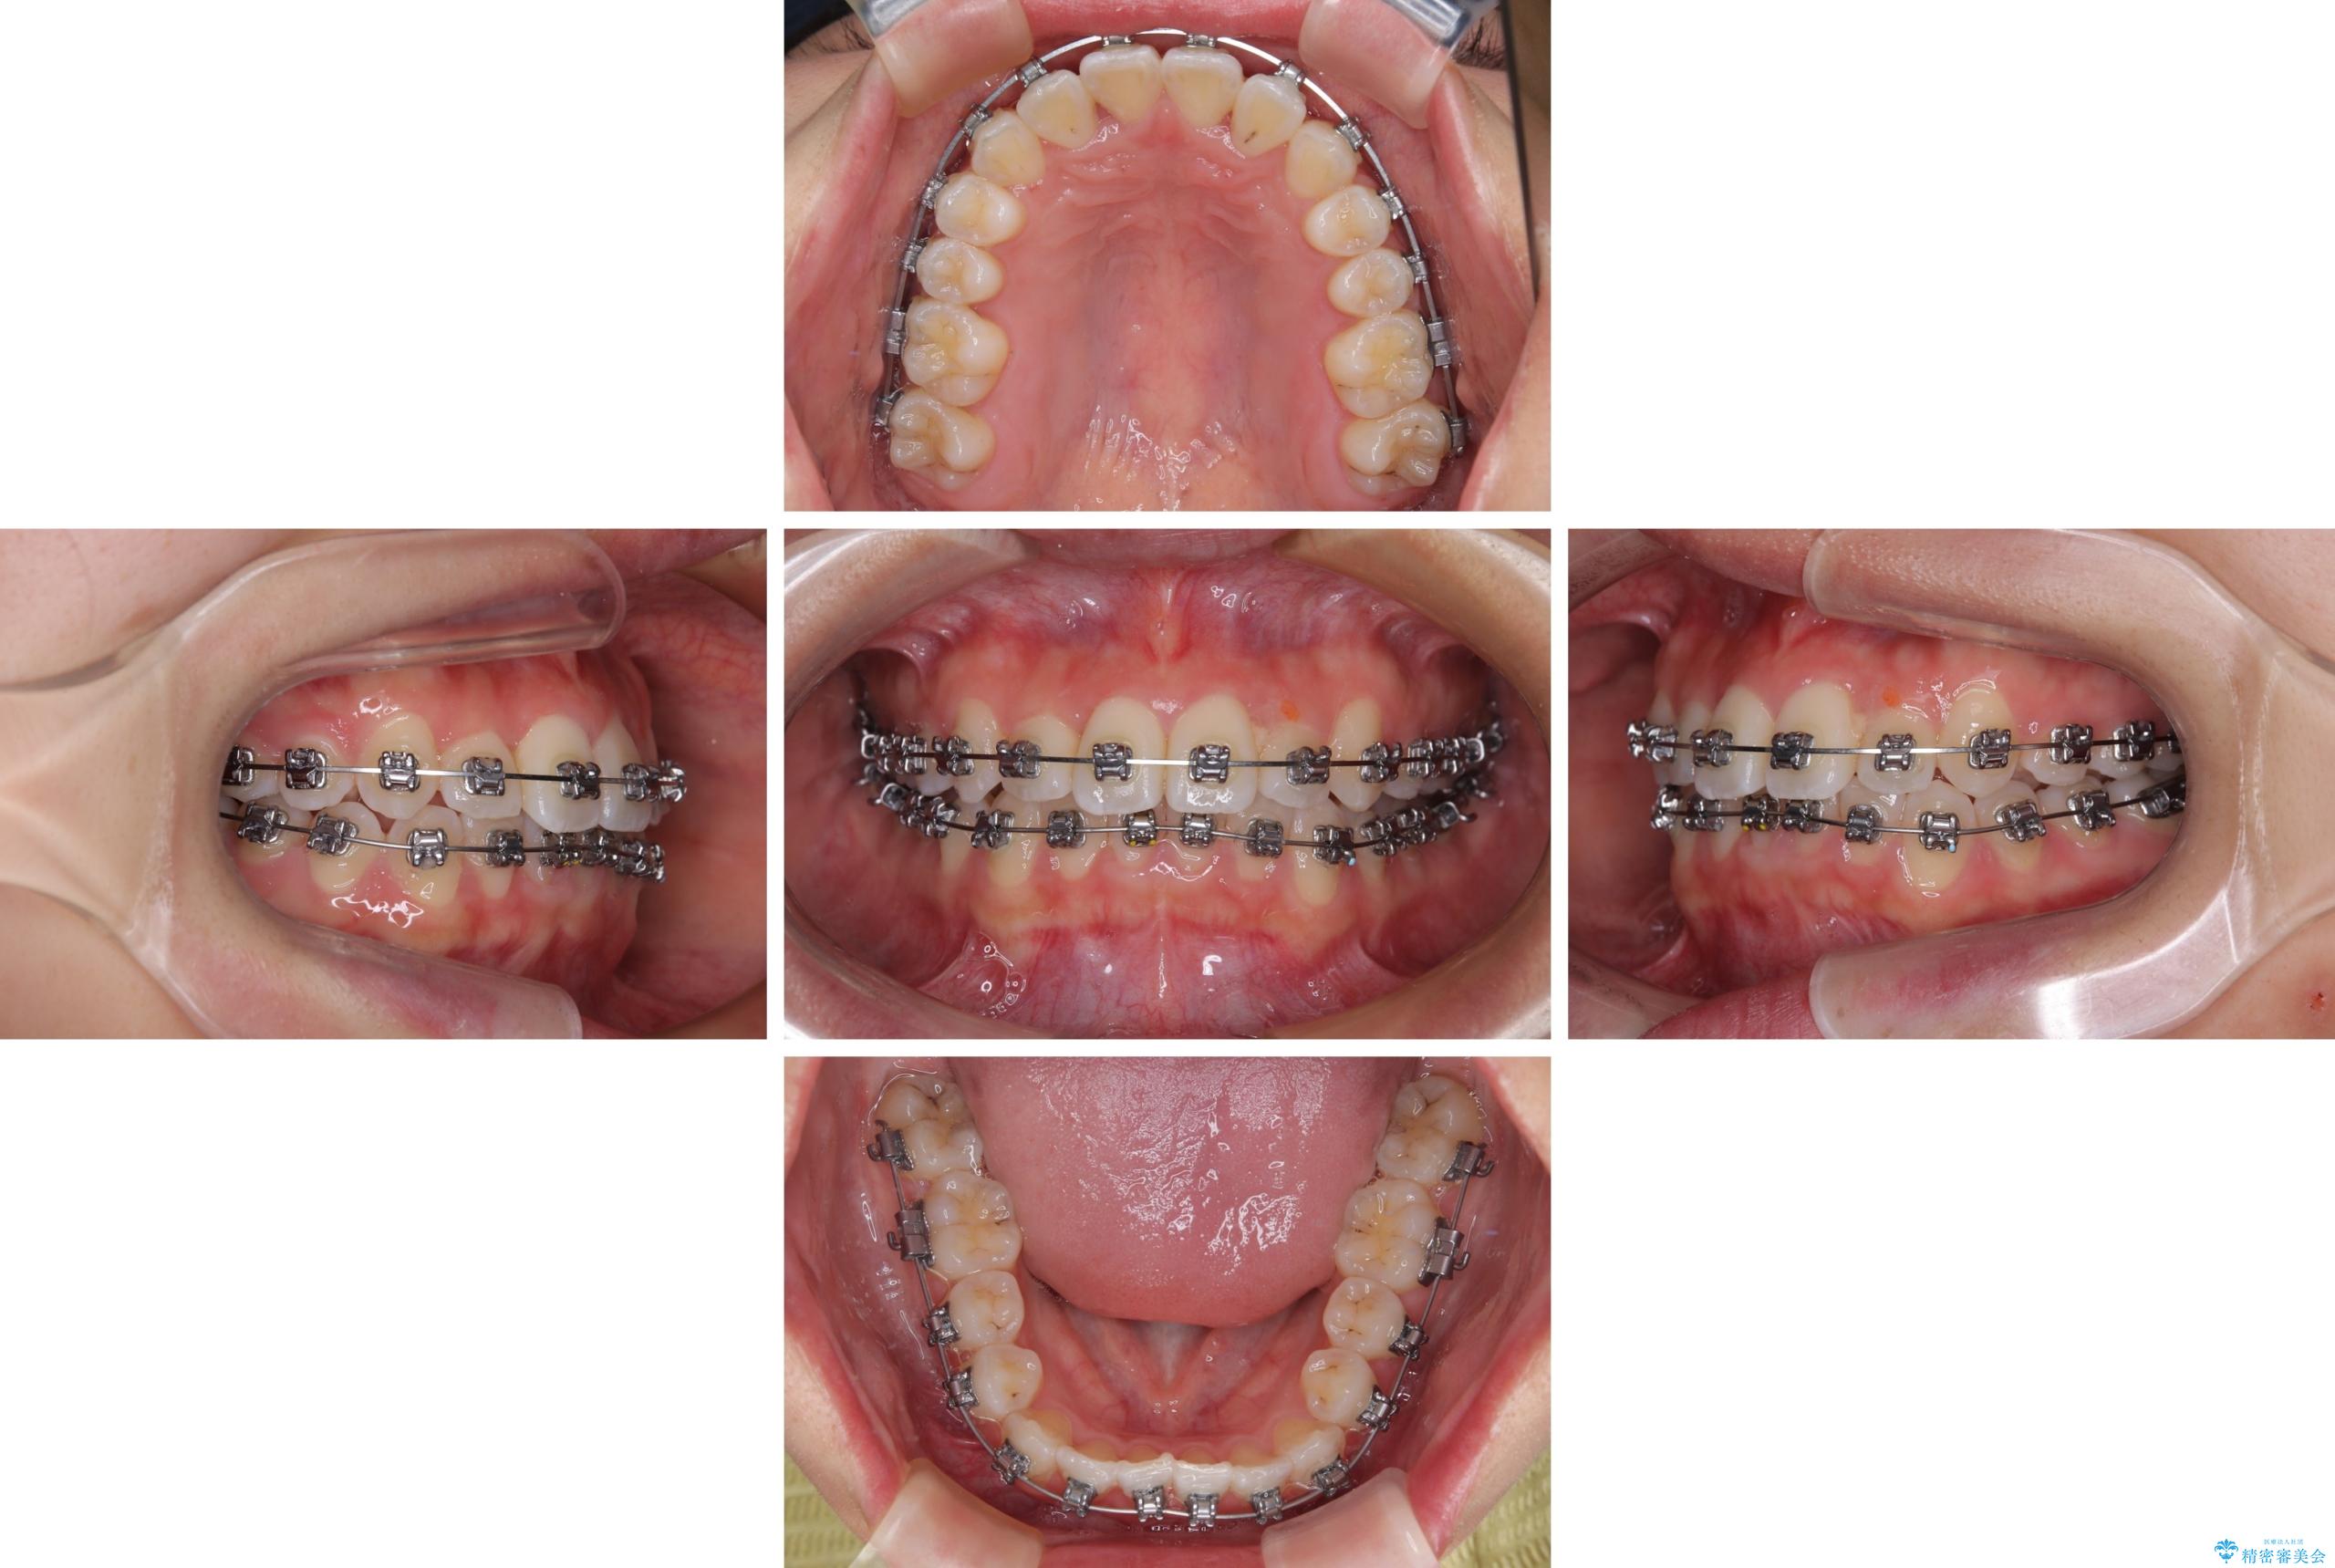

前歯のクロスバイト 裏側に隠れた歯をワイヤー装置で短期間治療

- 上顎前歯のクロスバイトを気にして来院された患者様です。

ワイヤー矯正でもマウスピース矯正でも対応可能でしたが、マウスピースによる自己管理に一切の自信がないとのことで、ワイヤー装置にて矯正治療を行うこととしました。

装置の外見を気にしていましたが、短期間で治療を終えることができるだろうと伝えると、安価であるメタルブラケットを選択されました。

想定通り、1年強で綺麗に仕上げることができました。